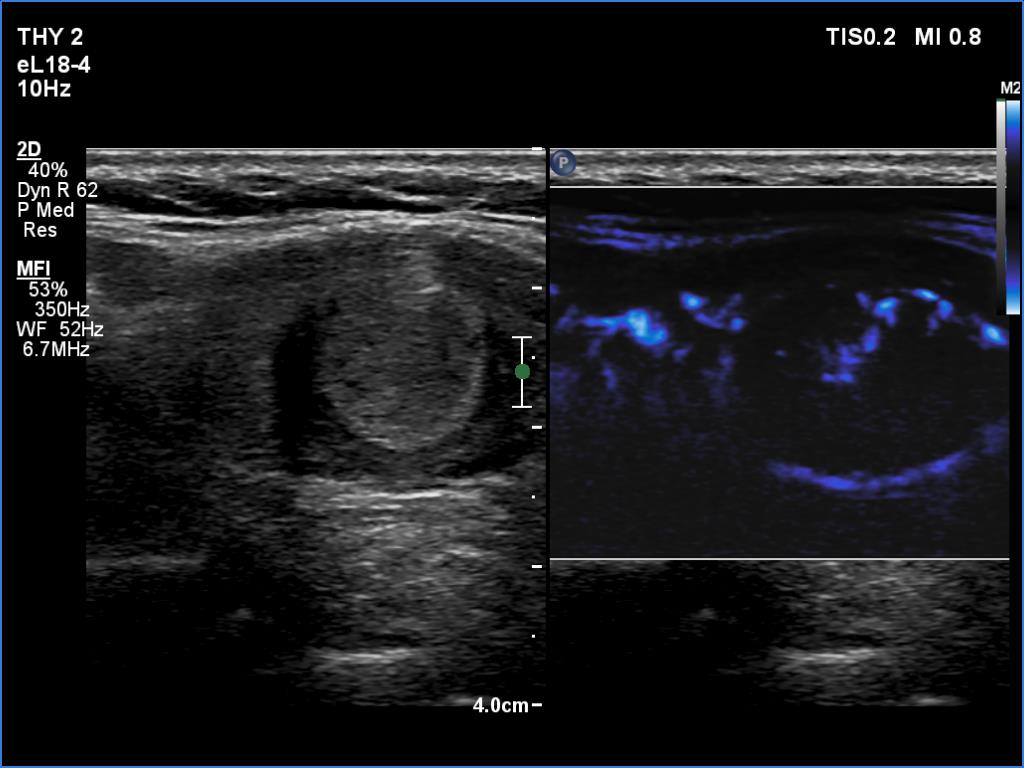

Right lobe, longitudinal scan

Left lobe, longitudinal scan, microflow imaging. There are vessels running around and also within the nodule.